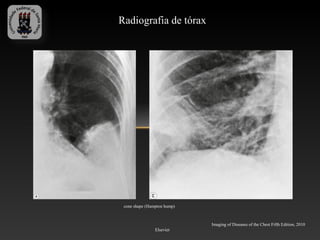

Radiografia de tórax

cone shape (Hampton hump)

Imaging of Diseases of the Chest Fifth Edition, 2010

Elsevier